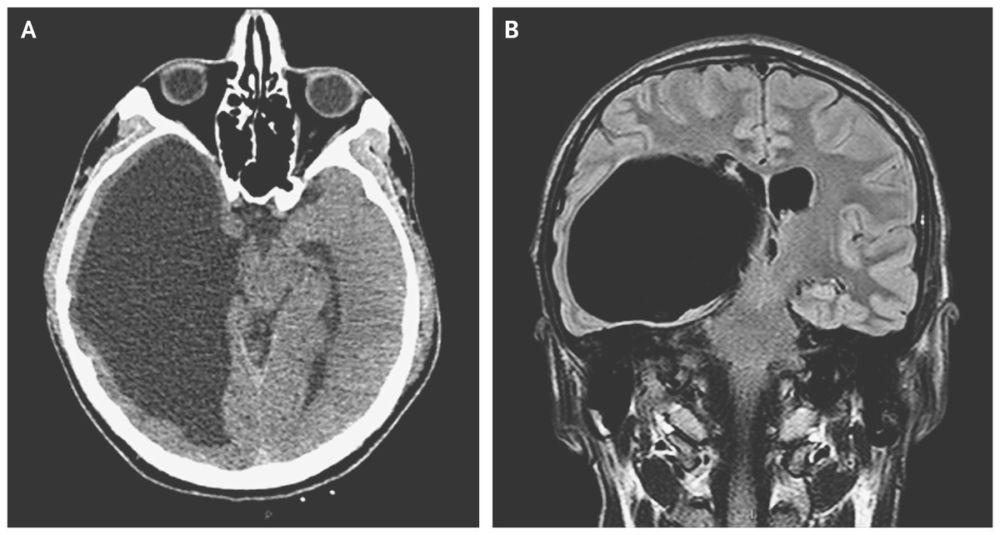

A CT scan of the brain (Panel A) showed an incidental finding of grossly dilated occipital and temporal horns of the right lateral ventricle.

Magnetic resonance imaging (Panel B) confirmed the presence of a large cystic lesion extending from the temporal and posterior horns of the right lateral ventricle (axial size, 11 cm by 7 cm), with a mild midline shift of the third ventricle, and compression of the midbrain and brain stem with thinning of the temporal and occipital cortexes. A large, asymptomatic, intraventricular arachnoid cyst was diagnosed.